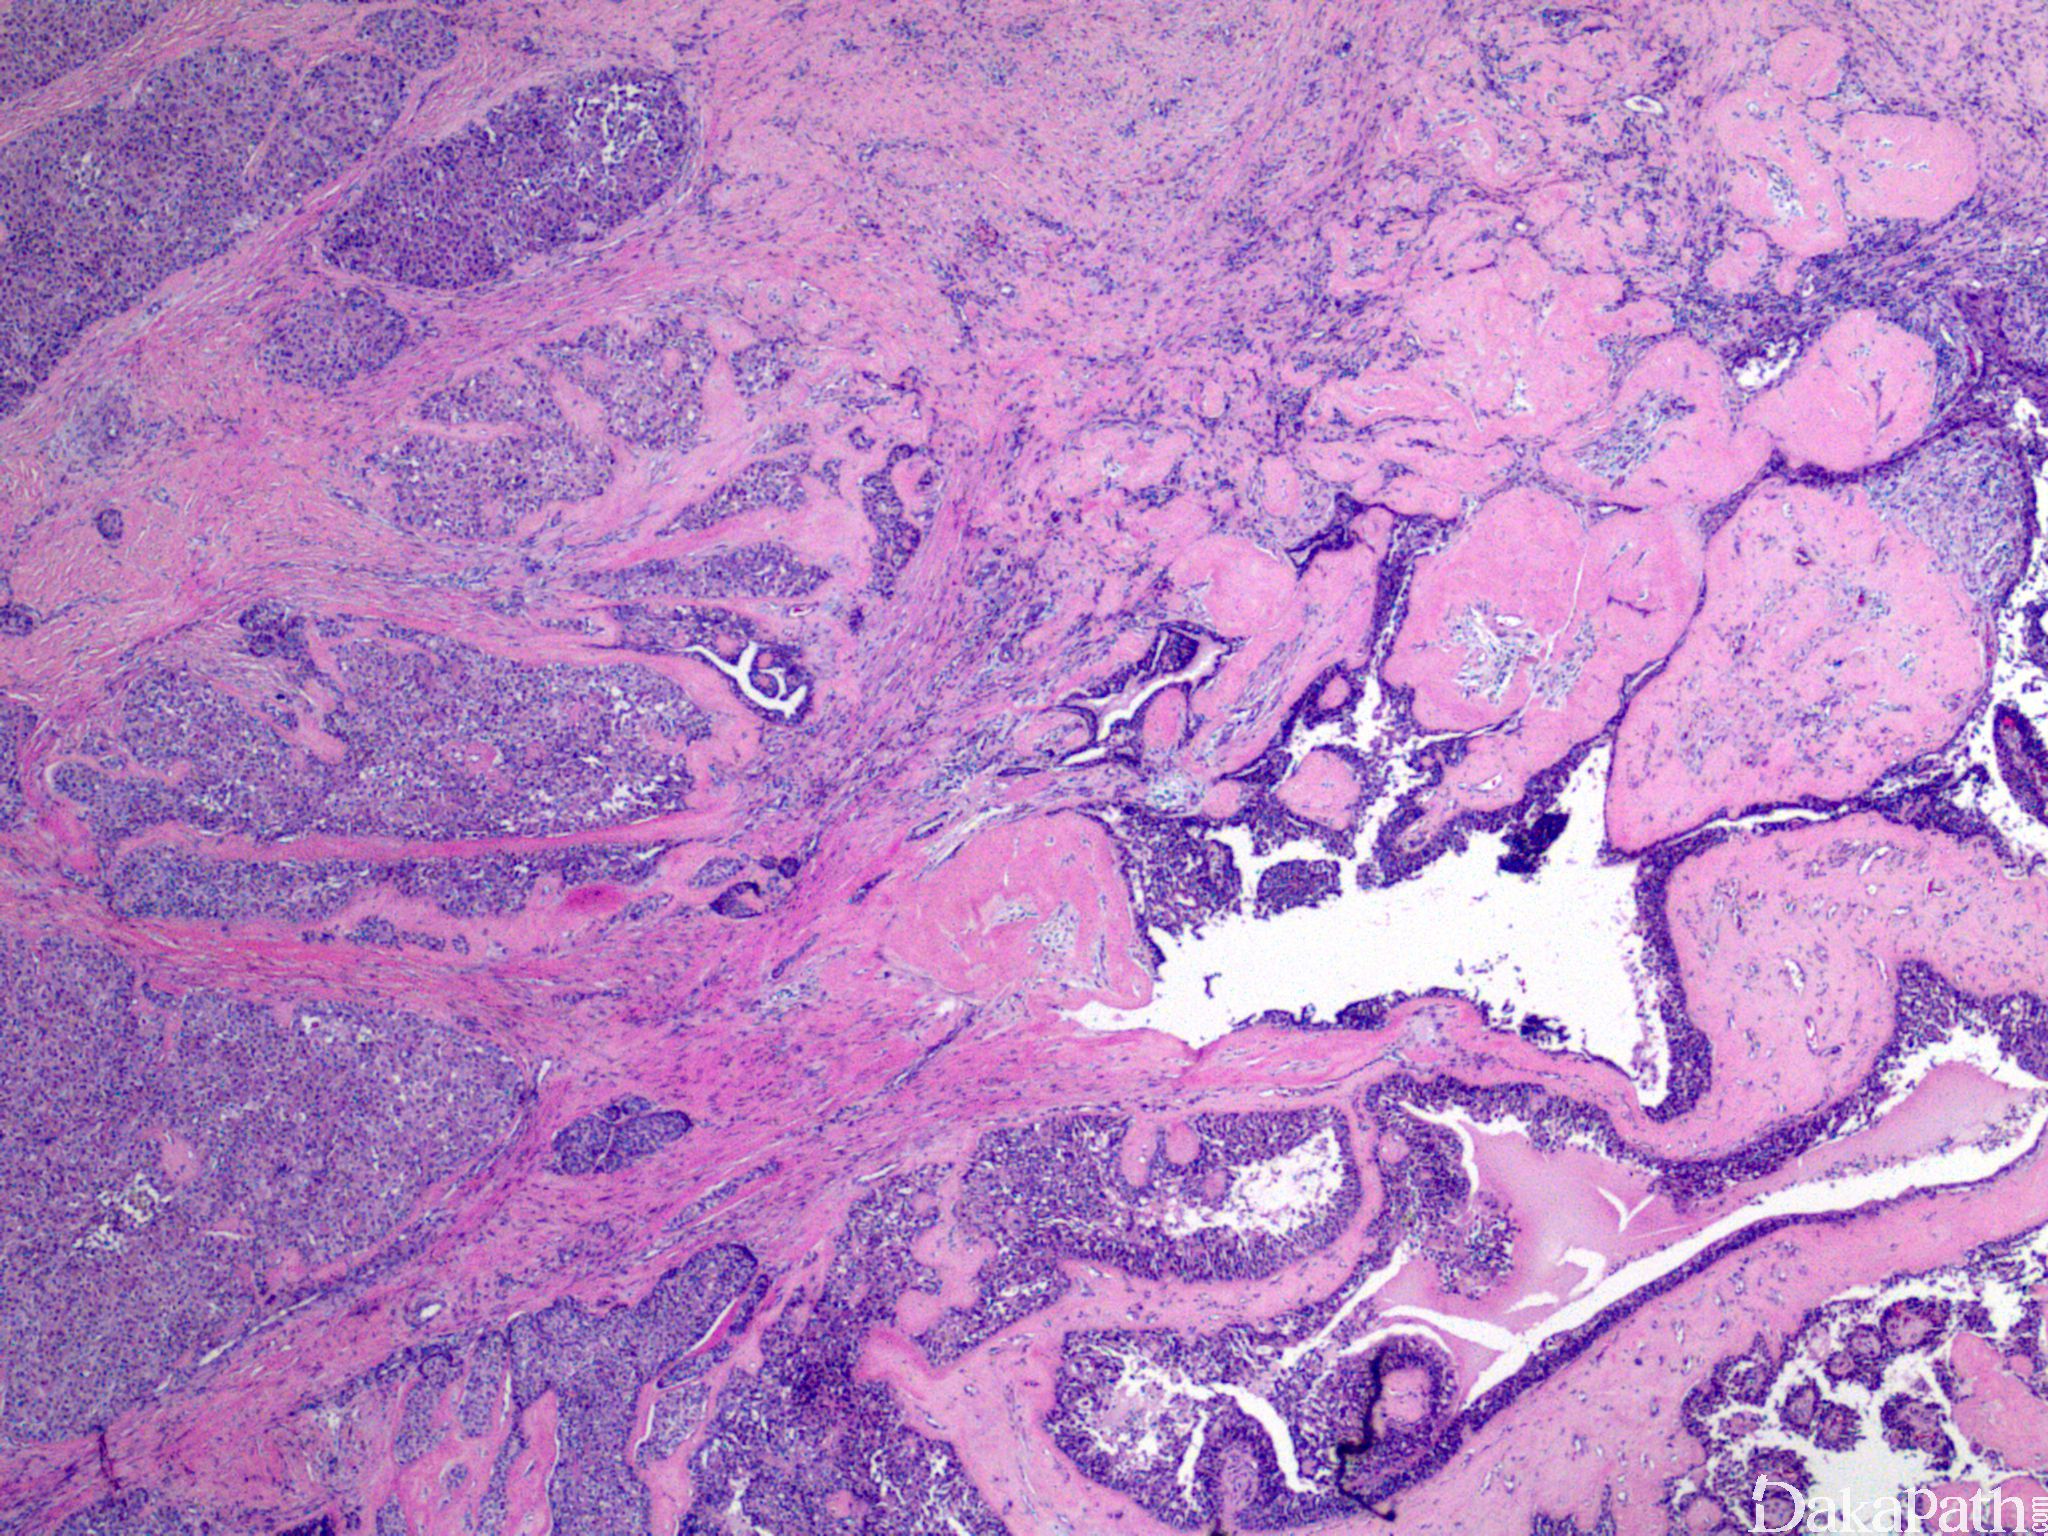

具有典型汗腺瘤形态学特征,呈囊性结节性生长,具透明细胞、鳞样细胞、肌上皮细胞等多种细胞成分;

具浸润性生长方式;

细胞具异型性,核分裂像常见,可伴坏死。